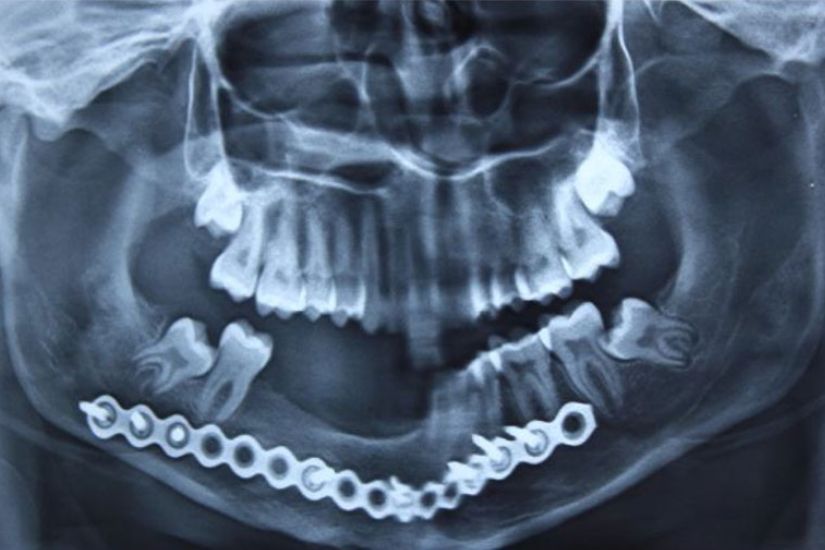

Dental Rehabilitation Using Alpha Dent Implant in Case of Reconstructed Mandible after Excision of Ossifying Fibroma

Dental Rehabilitation Using Alpha Dent Implant in Case of Reconstructed Mandible after Excision of Ossifying Fibroma Dr. Parit Ladani MDS